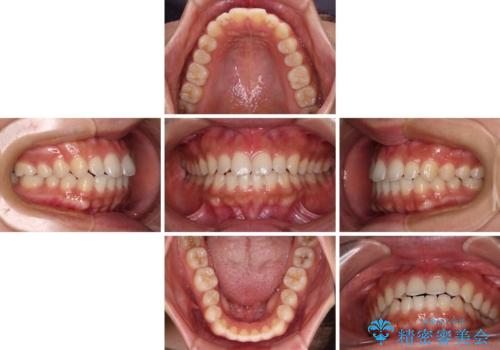

インビザラインを用いた上顎の部分矯正

- インビザライン・ライト

- 1年5ヶ月

- 上顎前歯の叢生を気にして来院された患者様です。

下顎前歯や上下奥歯の咬み合わせには殆ど問題がないため、上顎前歯のみを矯正する治療を提案しました。

ワイヤー装置でもインビザラインでも可能でしたが、前歯のみをきれいに排列するのであればインビザラインの方が仕上がりが良いので、インビザライン・ライトにて治療を行うこととしました。

インビザライン・ライトは、製作できるアライナーの枚数に制限があるため、移動可能な量に限りがあります。

一方で、半年から1年程度で治療を終えることができるため、軽度の歯列不正の患者様には大変お勧めです。